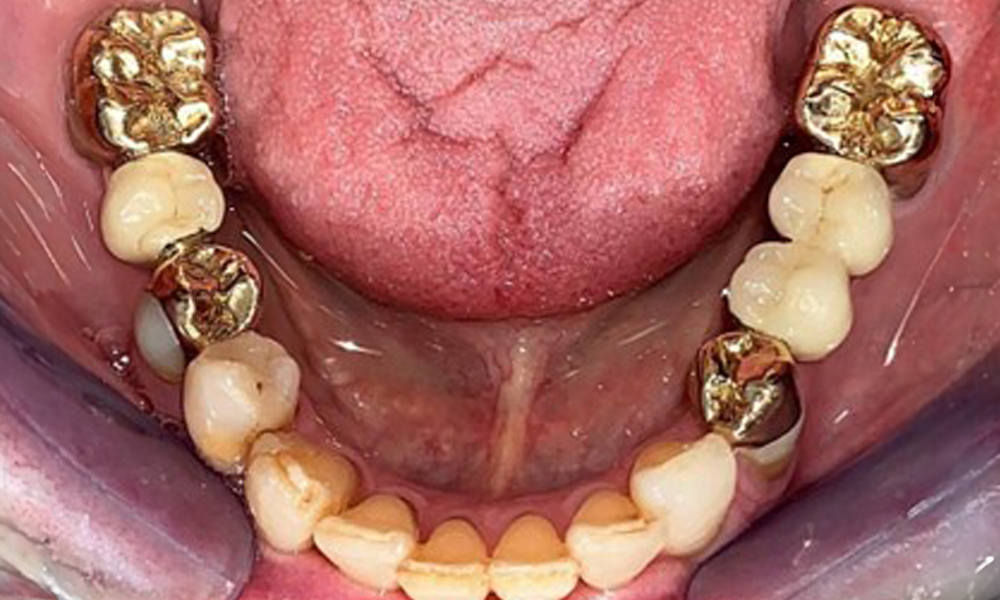

The dental findings are as follows: Combined removable implant and tooth-supported telescopic prostheses on implants 15, 13, 21, 23, 24, 25 and tooth 11 (Fig. 1, Fig. 2, Fig. 3). The patient was fitted with a fixed mandibular denture. Adequate bridges were present over 37 to 34 and 45 to 47 (Fig. 4), the crown margins were intact and there were no active caries. A composite filling with a marginal gap was present on tooth 43. There was mandibular gingival recession, exposing 1 to 3 mm of root surface. This also applies to 11.

Occlusal view of the mandible.

Fig. 4: Occlusal view of the mandible.

Radiological findings

The radiological findings show partially edentulous dentition with maxillary implants for teeth 15, 13, 21, 23, 24, 25 and a telescopic crown on tooth 11. Adequate mandibular bridges spanning 37 to 34 and 45 to 47 are present. 48 is impacted. There are suspected secondary caries distally on 43 and mesially on 44. 44 is restored with a non-radiopaque cavity lining. There is generalised horizontal bone loss of approx. 10% to 30% and localised vertical bone loss affecting teeth 22 and 42 (Fig. 5).